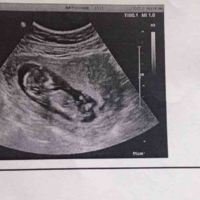

孕11周唐氏筛查跟孕12周nt检查都过了胎儿畸形风险相对较小。唐氏综合征筛查和NT(颈部透明带厚度)筛查是两种不同的产前筛查方法,用于评估胎儿患染色体异常(如唐氏综合征)和其他畸形的风险。如果唐氏和NT结果均为正常,即胎儿患染色体异常和其他畸形的风险较低,那么胎儿的畸形风险相对较小。但这并不能完全排除胎儿患畸形的可能性,因为产前筛查只能提供相对的风险评估,而不能做出确诊。NT跟唐氏筛查都是孕期非常

医生说做了11周做了nt检查后16周就不用做唐筛了,这是正常的。根据医生的建议,通常在进行了NT(孕妇孕早期唐氏筛查)检查后,如果结果正常,16周时通常不需要再进行唐氏筛查。这是因为NT检查是一种较早期的筛查方法,能够初步排除胎儿患唐氏综合征的风险。而16周时,医生可能会根据孕妇的具体情况和检查结果来综合考虑是否需要进一步的筛查或检查。因此,医生会建议有些孕妇就不用再做唐筛了,这是正常的。NT检查

在孕期产前检查中,胎儿颈项透明层(Nuchal translucency,NT)是一项非常重要的指标。NT是通过B超技术在10-14周孕周内测量的,它是指位于胎儿颈部皮下的液体层的厚度。NT值的大小与胎儿染色体异常的风险密切相关,此外,也有人认为NT值的大小可以预测胎儿男女。那么,NT1.1mm是男孩还是女孩?接下来,我们一起来探讨一下。NT值与胎儿染色体异常风险正常情况下,NT值应该在2.5mm